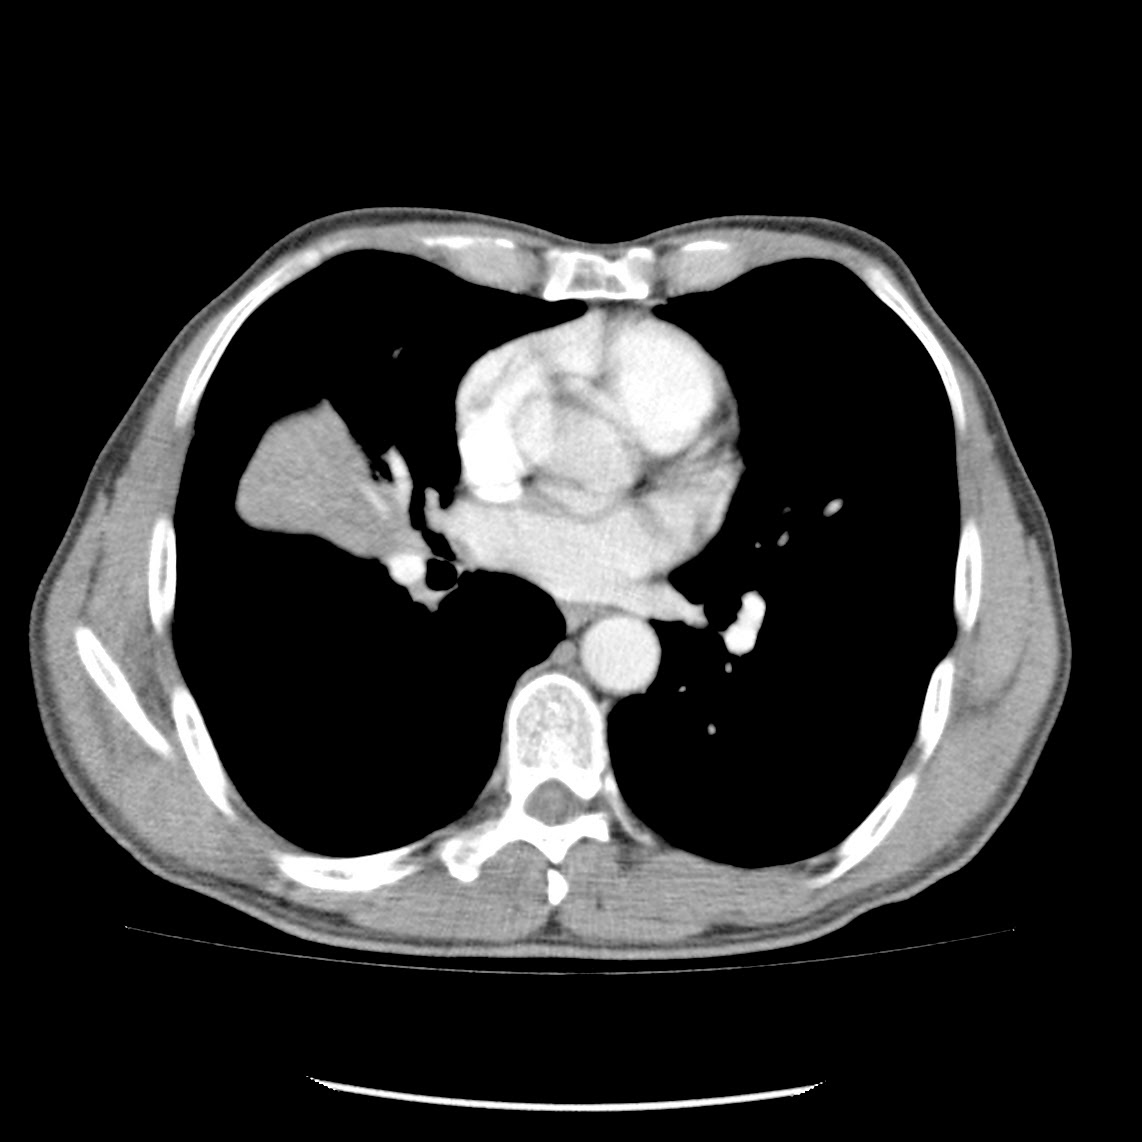

Caso interesante #6

Otro casito de un tórax para localizar la consolidación